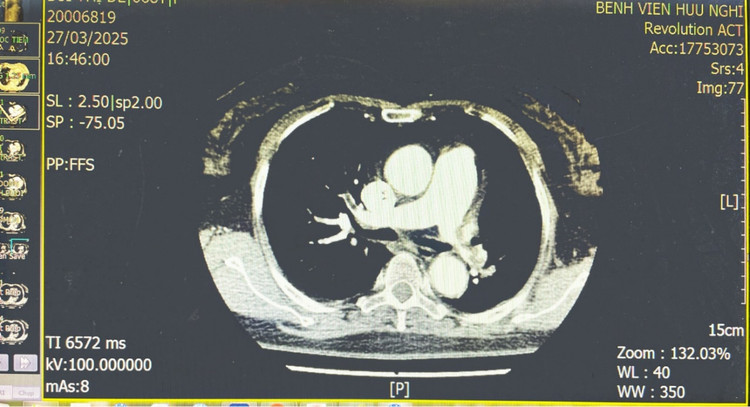

| Hình ảnh động mạch phổi bị tắc do huyết khối. |

Bệnh nhân sau đó được hội chẩn đa chuyên khoa gồm: Cấp cứu, Tim mạch, Tim mạch can thiệp, Chẩn đoán hình ảnh, Dược lâm sàng và khẩn trương được tiến hành siêu âm tim, siêu âm mạch chi dưới, chụp cắt lớp vi tính động mạch phổi và các xét nghiệm chẩn đoán cần thiết. Kết quả, bệnh nhân được chẩn đoán tắc động mạch phổi cấp có biến chứng suy hô hấp và rối loạn về huyết động.